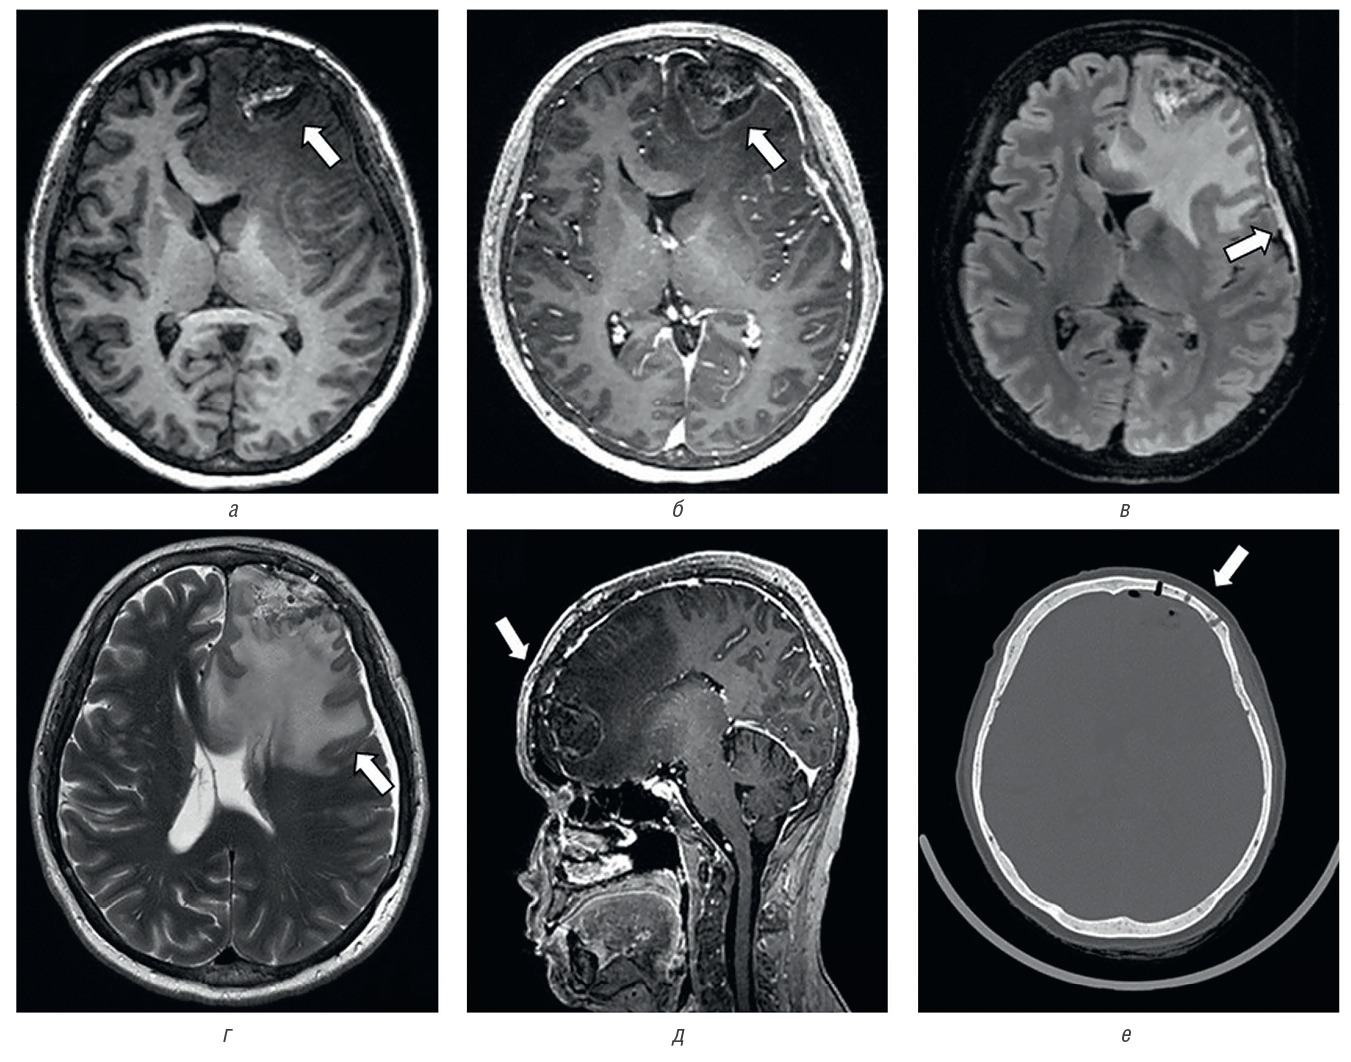

Операция 25.08.2022: микрохирургическое удаление опухоли левой лобной доли с применением нейрофизиологического мониторинга. Удаление образования кожи волосистой части головы в лобной области. Весь удаленный материал отправлен на прижизненное патологоанатомическое исследование. Состояние пациентки после операции стабильное. По контролю МРТ ГМ состояние после костно-пластической трепанации черепа в левой лобной области по поводу оперативного удаления опухоли левой лобной доли с признаками выраженного вазогенного отека в левых лобной и островковой долях с распространением на мозолистое тело и формированием участка гипоперфузии латерально от полости. Дислокация срединных структур вправо до 0,5 см. Вклинение левой поясной извилины под фалькс. Хроническая субдуральная гематома слева. Пневмоцефалия (рис. 3).

Рис. 3. МРТ и КТ головного мозга. Опухоль левой лобной доли, состояние после хирургического удаления опухоли: a — МРТ в режиме IR-FSPGR в аксиальной проекции, отмечается постоперационная полость (стрелка), выполненная ликворным и геморрагическим содержимым; б — МРТ в режиме IR-FSPGR с контрастным усилением в аксиальной проекции, отмечается умеренное, неравномерное накопление контрастного препарата по периферии послеоперационной полости (стрелка); в — МРТ в режиме Т2-FLAIR в аксиальной проекции, субдурально определяется серповидный участок повышенного относительно ликвора МР-сигнала толщиной до 0,7 см; г — МРТ в режиме Т2 в аксиальной проекции, отмечается распространенная зона вазогенного отека вещества головного мозга левого полушария с признаками дислокации срединных структур и боковых желудочков; д — МРТ в режиме IR-FSPGR с контрастным усилением в сагиттальной проекции; е — КТ головного мозга, костный режим, определяется зона оперативного доступа (стрелка), костный лоскут располагается ровно

Fig. 3. MRI and CT of the brain. Tumor of the left frontal lobe, a condition after surgical removal of the tumor: a — MRI in IR-FSPGR mode in axial projection, there is a postoperative cavity (arrow) made with cerebrospinal fluid and hemorrhagic contents; б — MRI in the IR-FSPGR mode with contrast enhancement in the axial projection, there is a moderate, uneven accumulation of contrast agent along the periphery of the postoperative cavity (arrow); в — MRI in T2-FLAIR mode in axial projection, subdurally determined sickle-shaped area of increased relative to the cerebrospinal fluid MR signal thickness up to 0.7 cm; г — MRI in T2 mode in axial projection, there is a common area of vasogenic edema of the brain substance of the left hemisphere with signs of dislocation of median structures and lateral ventricles; д — MRI in IR-FSPGR mode with contrast enhancement in sagittal projection; е — CT of the brain, bone mode, the zone of operative access is determined (arrow) the bone flap is located exactly